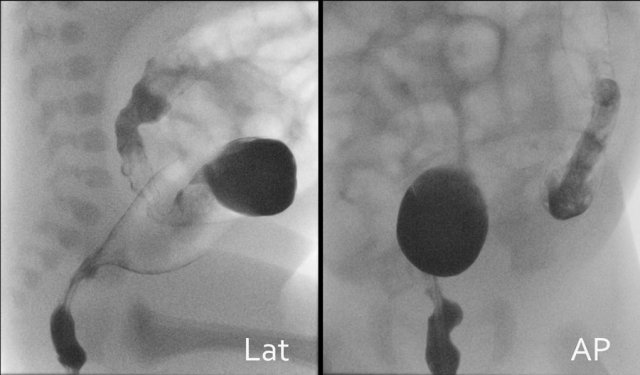

Lateral images from the rectum and sigmoid should be documented first followed by frontal images.

Focus on the diameter of the rectum versus the remainder of the colon, the presence of a microcolon and meconium pellets.

First look at the images of the upper GI-study and describe the findings.

Then continue reading.

The findings are:

- Dilated proximal duodenum (asterix)

- Small amount of contrast passes through the duodenal web to the distal duodenum (arrow)